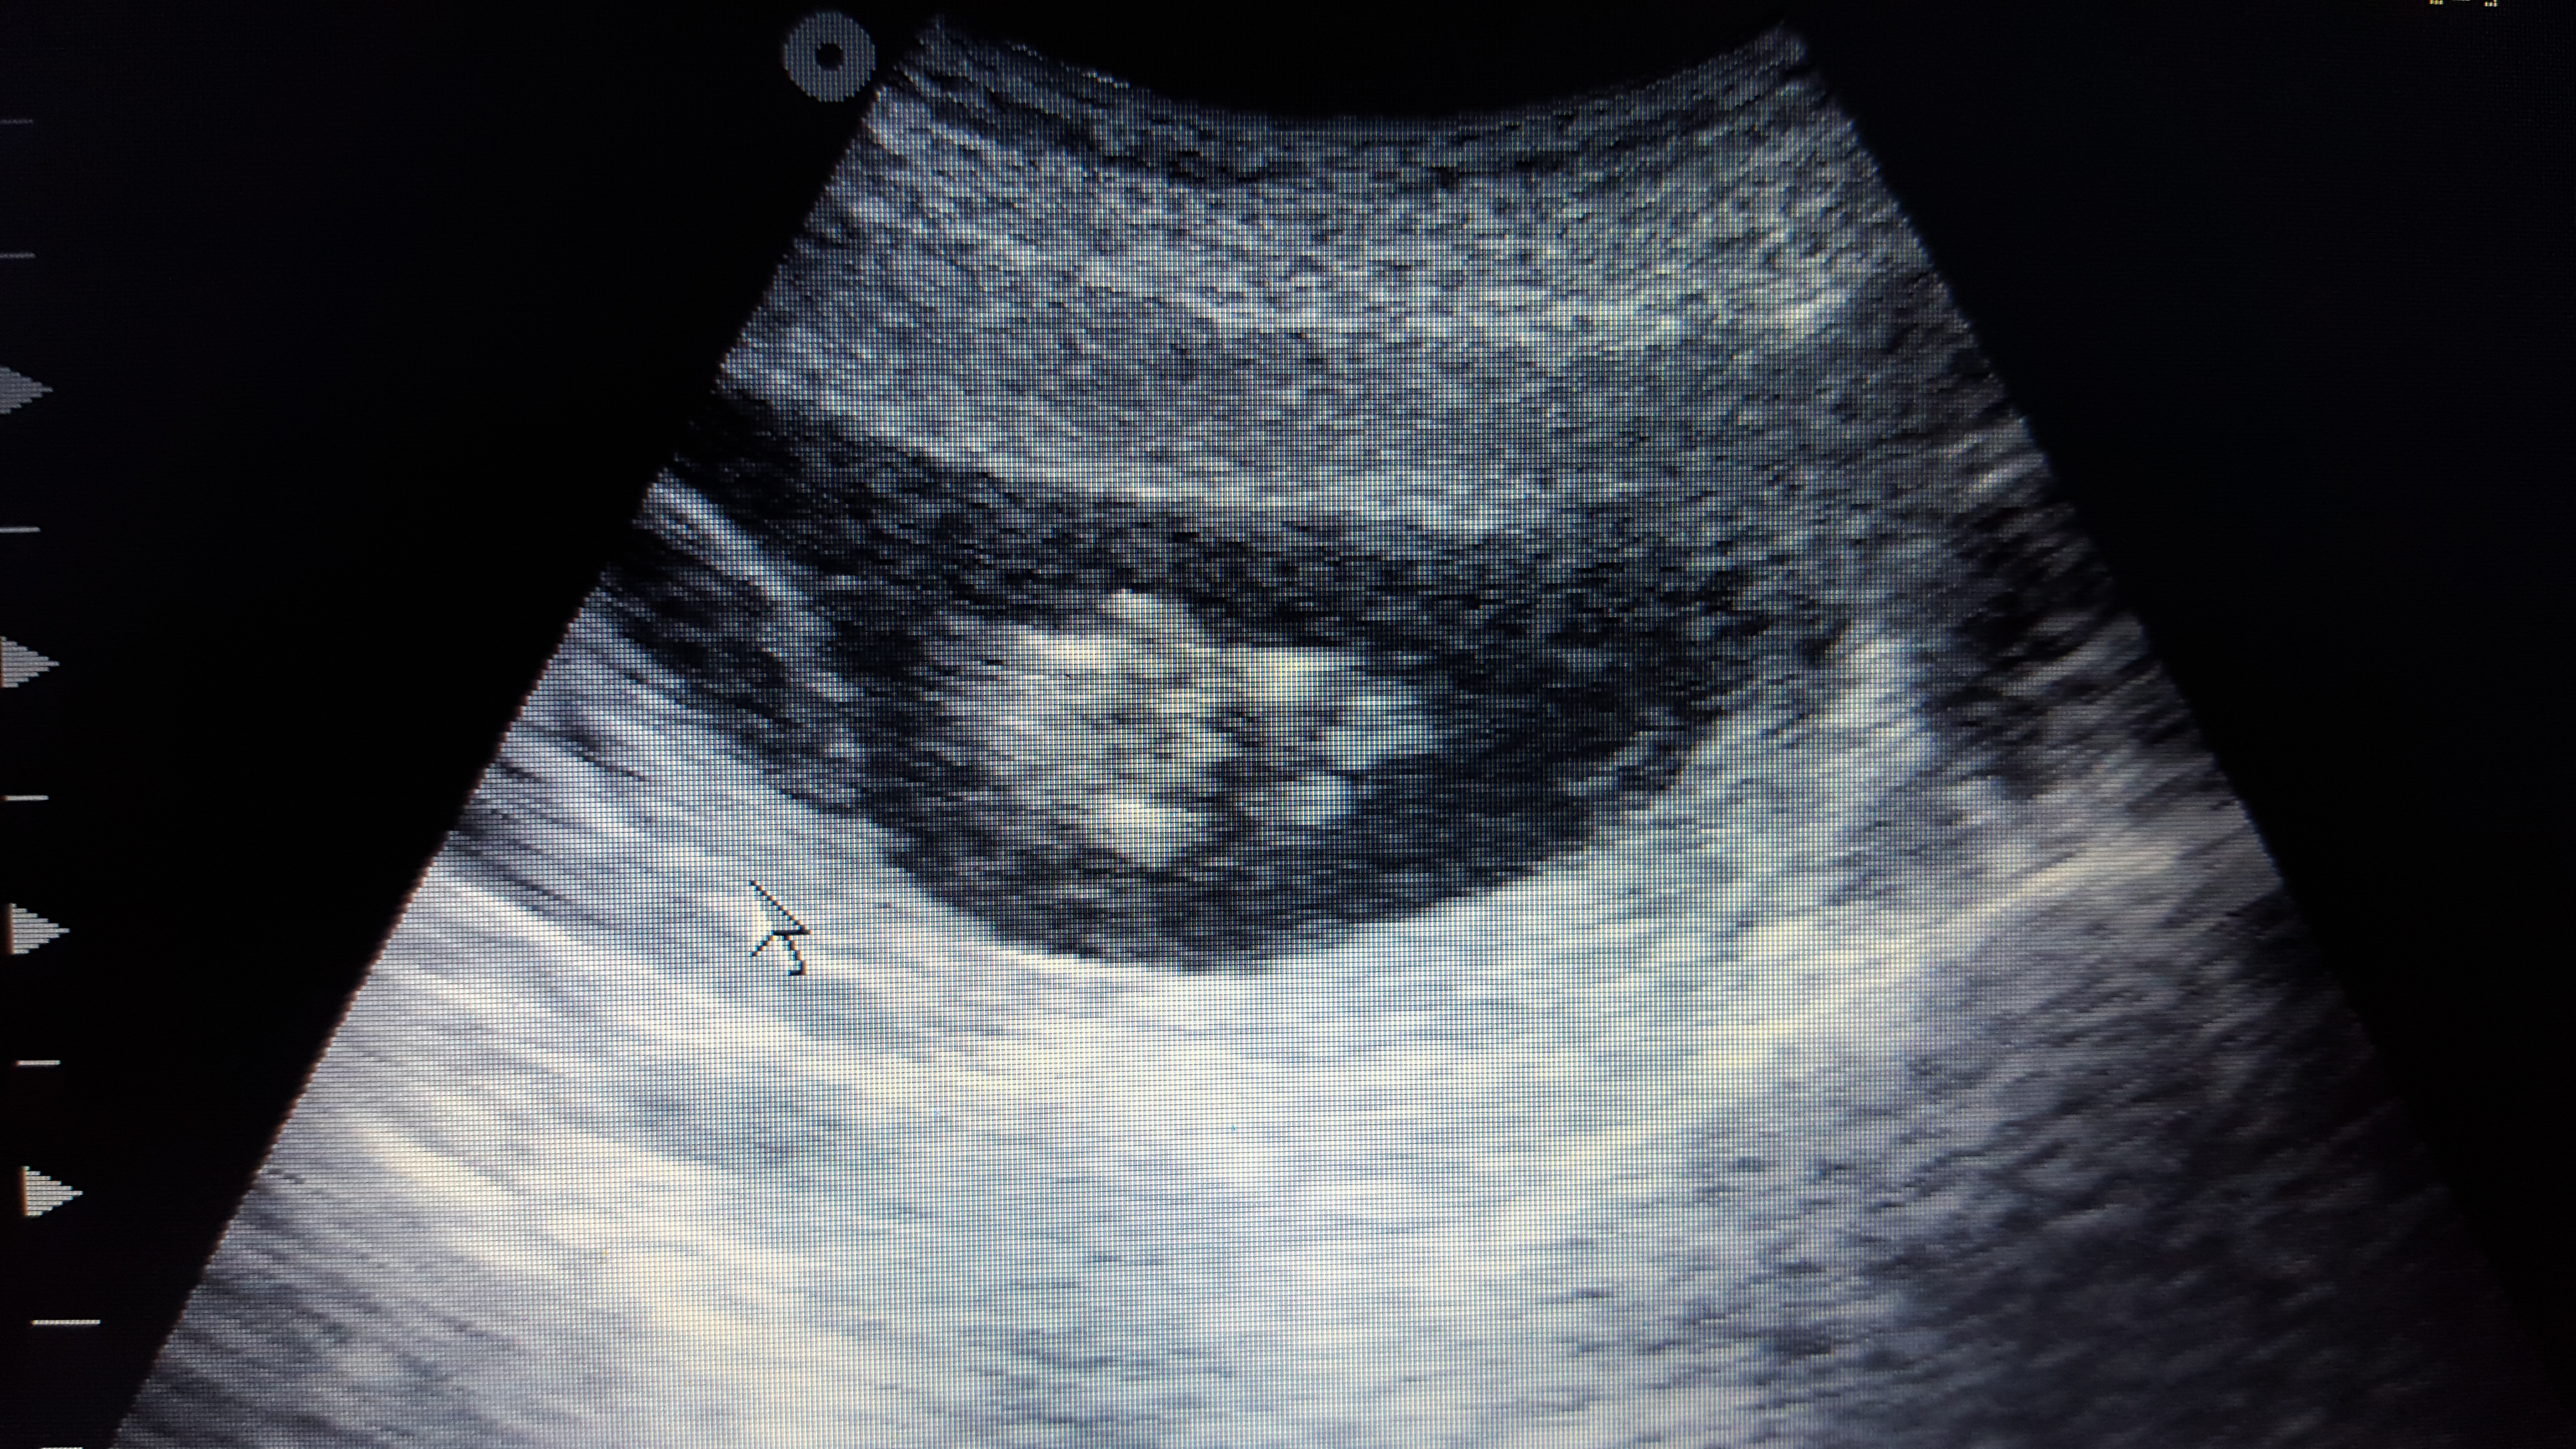

Pink or blue? These are taken at 13+3

Attachment 29188

Babies hands were around genital area alot so may of caught that in some of the photos!

For the nub i lean girl.